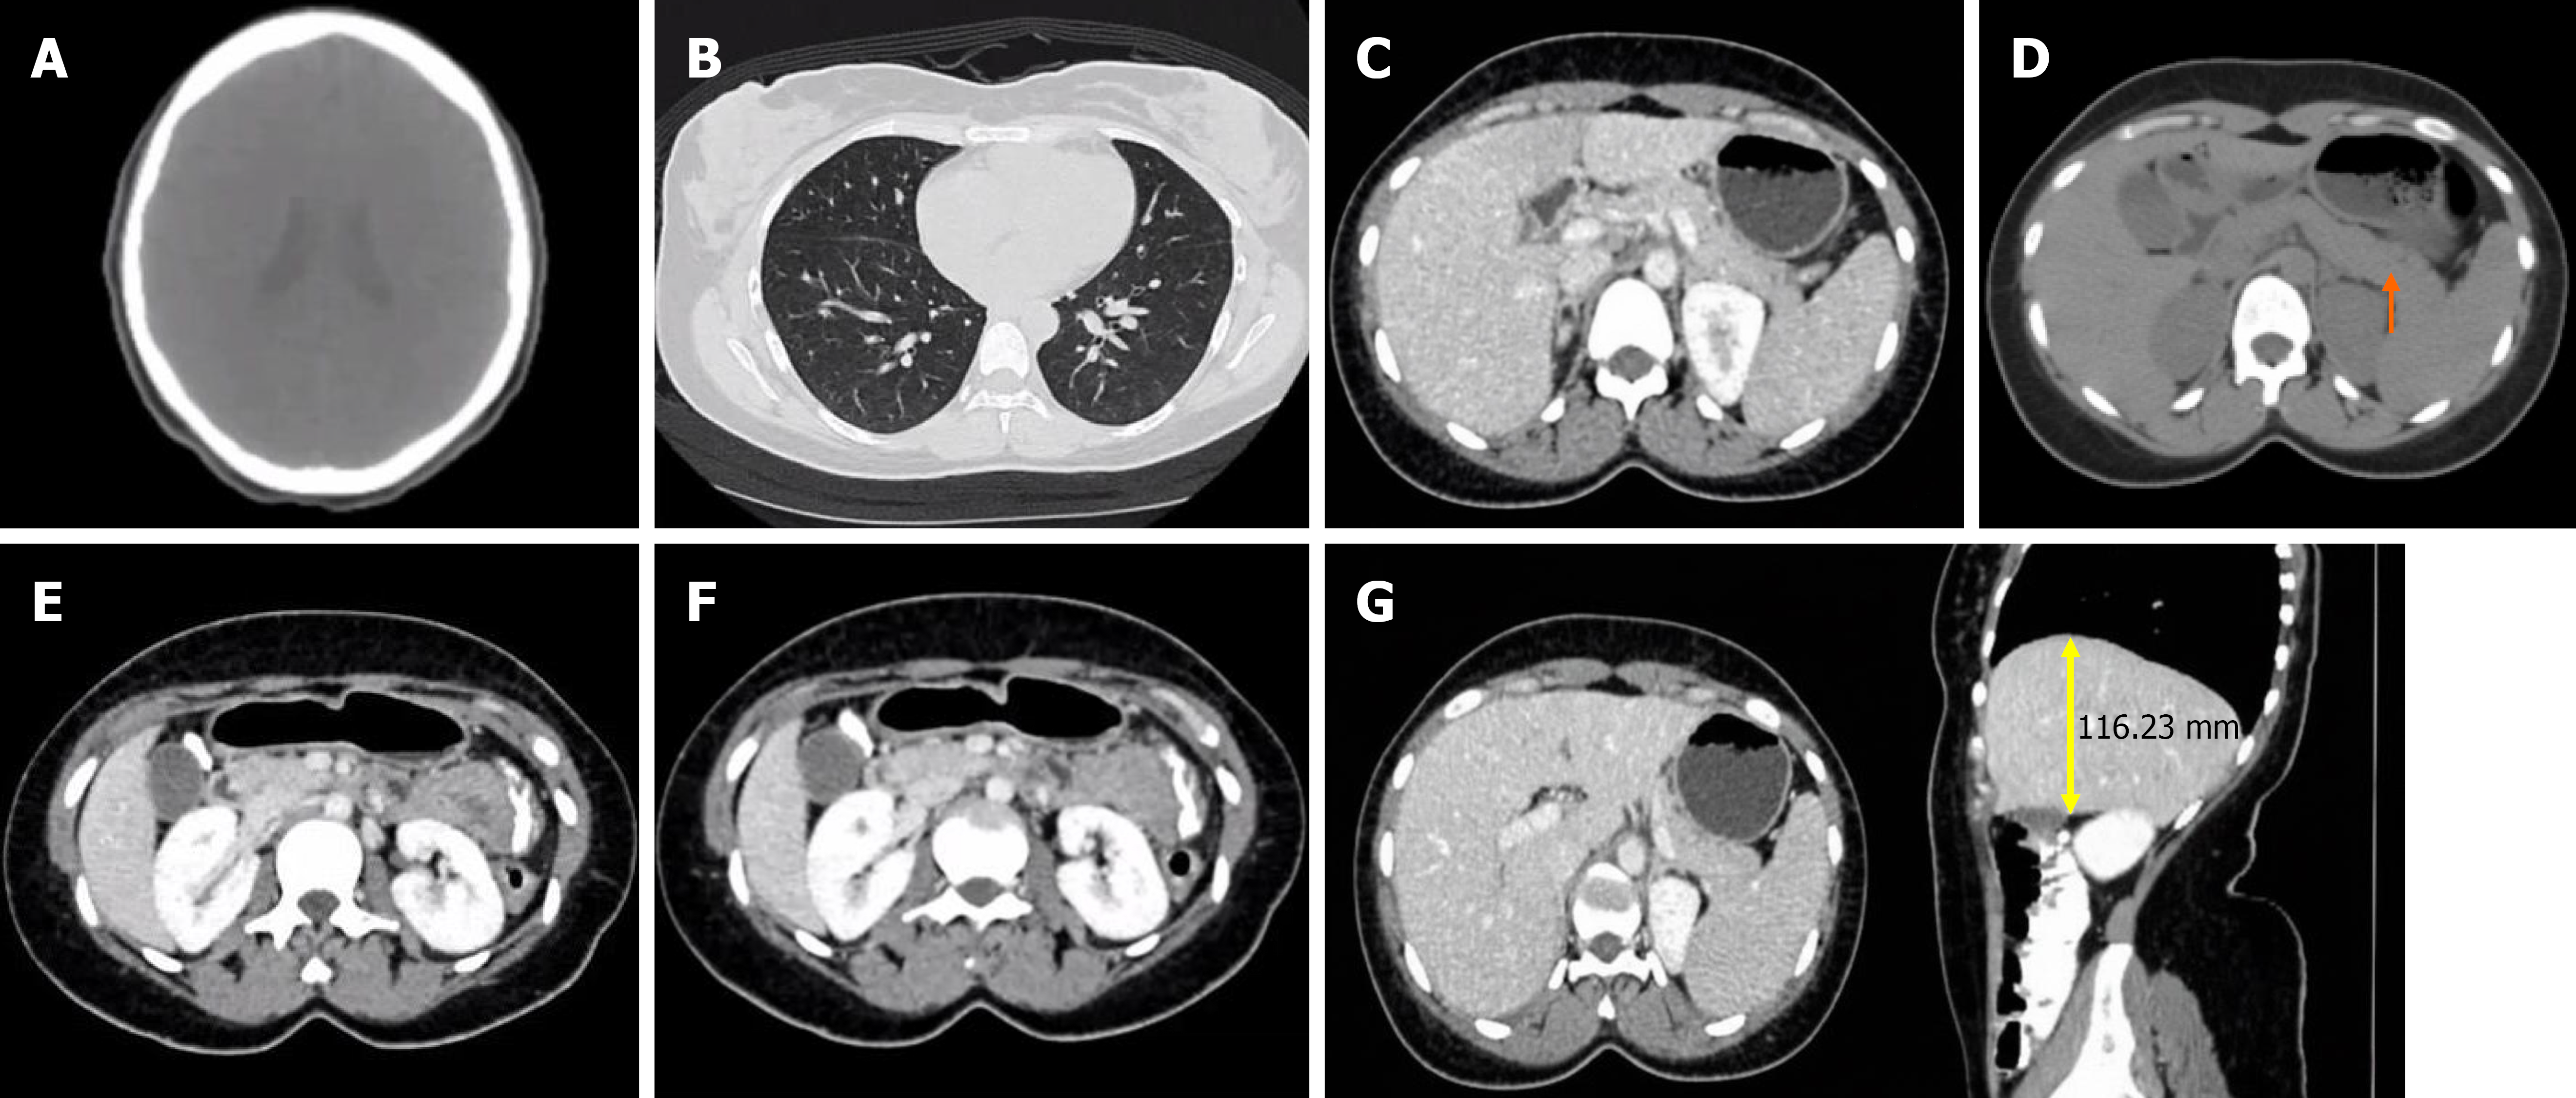

Figure 2 Computed tomography findings.

A: Normal head computed tomography (CT), no metastases; B: Normal chest CT, no lung metastases, no pulmonary or mediastinal lesions; C: Abdominopelvic CT scan showing bulky body and tail of pancreas relative to head; D-G: Abdominopelvic CT showing normal gall bladder, kidneys, stomach, bowel loops and liver (span of 11.6 cm).